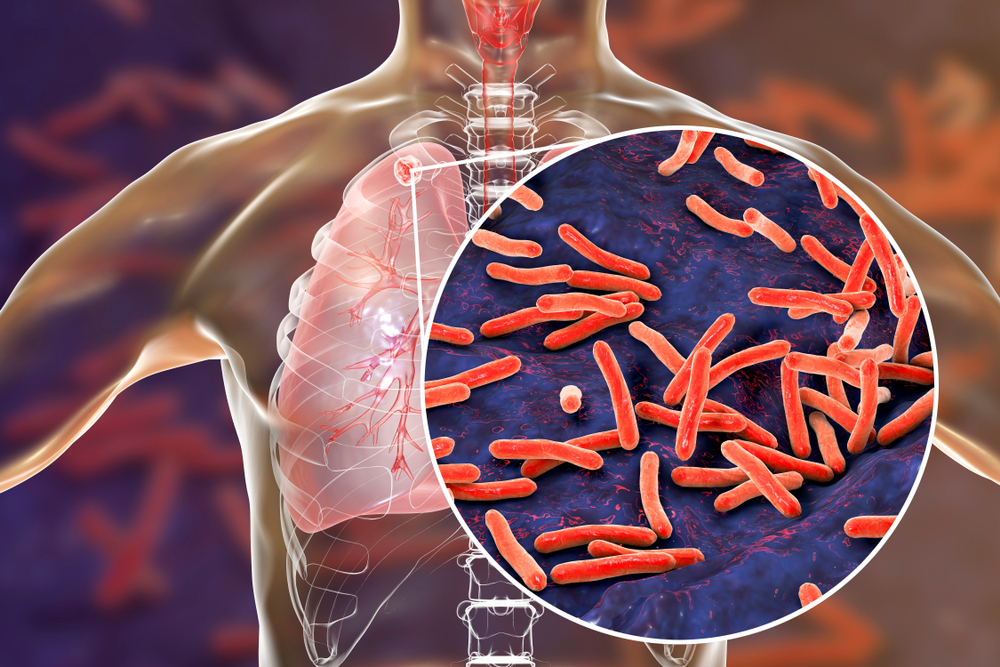

Симптомы туберкулеза: Как распознать и что делать